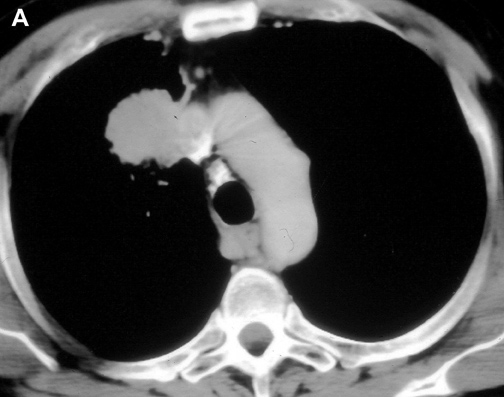

The anatomy of the SVC (Figure 1) and left brachiocephalic vein put this venous system in a critical area vulnerable to tumors arising both in the lung and anterior mediastinum. Malignant invasion is the most frequent indication for SVC resection and reconstruction. Lung cancer can involve the vessel with direct invasion by primary tumors arising in the right upper lobe or by nodal metastases (stations R2, R4 and 3) (Figure 2). Anterior mediastinal tumors (thymoma, thymic carcinoma, germ cell tumors, etc) may involve directly both the SVC and the left brachiocephalic vein (Figure 3). Primary tumors of the SVC represent a rare indication for surgery. Other infrequent indications are saccular aneurysms or primary malformations and traumatic lesions (iatrogenic, blunt, or penetrating injuries).

| Figure 2A & B. (A) Lung cancer invading the superior vena cava. (B) Mediastinal lymph nodes invading the superior vena cava. | Figure 3. Cortical thymoma invading the superior vena cava. | |